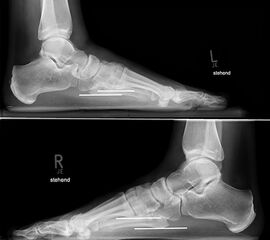

In der seitlichen Aufnahme ist auf Dislokationen und Subluxationen in den Tarsometatarsalgelenken sowie auf einen Verlust des Fußlängsgewölbes zu achten. Bei Instabilitäten des 1. Strahls bzw. Abflachung des Fußlängsgewölbes tritt in der Seitaufnahme die plantare Kontur des Os cuneiforme mediale tiefer im Vergleich zur Basis des Metatarsale 5. Darüber hinaus sollte die Cyma-Linie im Bereich des Chopartgelenkes in der Seitaufnahme eine harmonische S-förmige Linie bilden.

Insbesondere bei rein ligamentären, aber auch subtilen Verletzungen können belastete Vergleichsaufnahmen der unverletzten Gegenseite oder Streßaufnahmen des verletzten Fußes unter Bildwandlerkontrolle hilfreich sein 161129584 (Richter 2007).